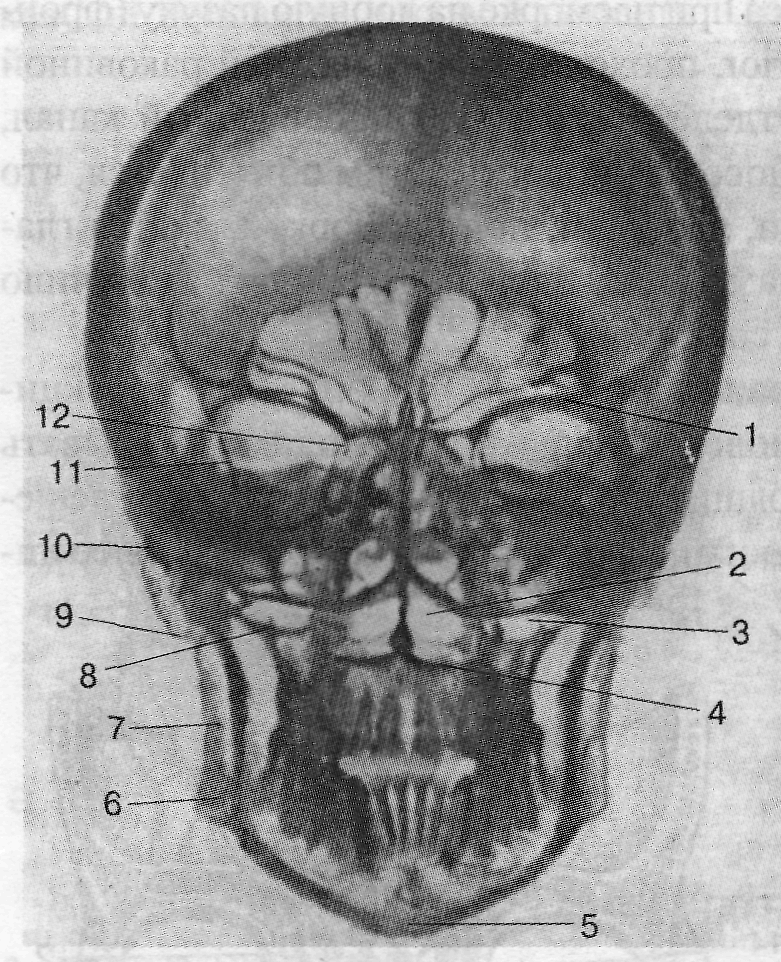

На рентгенограмме черепа в прямой проекции прежде всего необходимо обратить внимание на структуры, формирующие глазницы, полость носа, анатомические образования в области верхней челюсти, оцениваются форма, размеры и характер лобной и верхнечелюстной пазух, а также большое затылочное отверстие. На рентгенограмме в боковой проекции можно оценить черепные ямки, толщину и рельеф костей мозгового черепа. Особое внимание необходимо обратить на размеры и форму турецкого седла, клиновидной и лобной пазух. Оценка формы и размеров турецкого седла позволяет судить о его содержимом – гипофизе.

Рис. 3.31. Рентгенограмма черепа взрослого человека; передняя проекция.

1 – margo supraorbitalis; 2 – cavum nasi; 3 – sinus maxillaris; 4 – дно полости носа; 5 – protuberantia mentalis; 6 – angulus mandibulae; 7 – r. mandibulae; 8 – дно верхнечелюстной пазухи; 9 – processus mastoideus; 10 – facies externa basis cranii; 11 – ala major ossis sphenoidalis; 12 – fissura orbitalis superior.